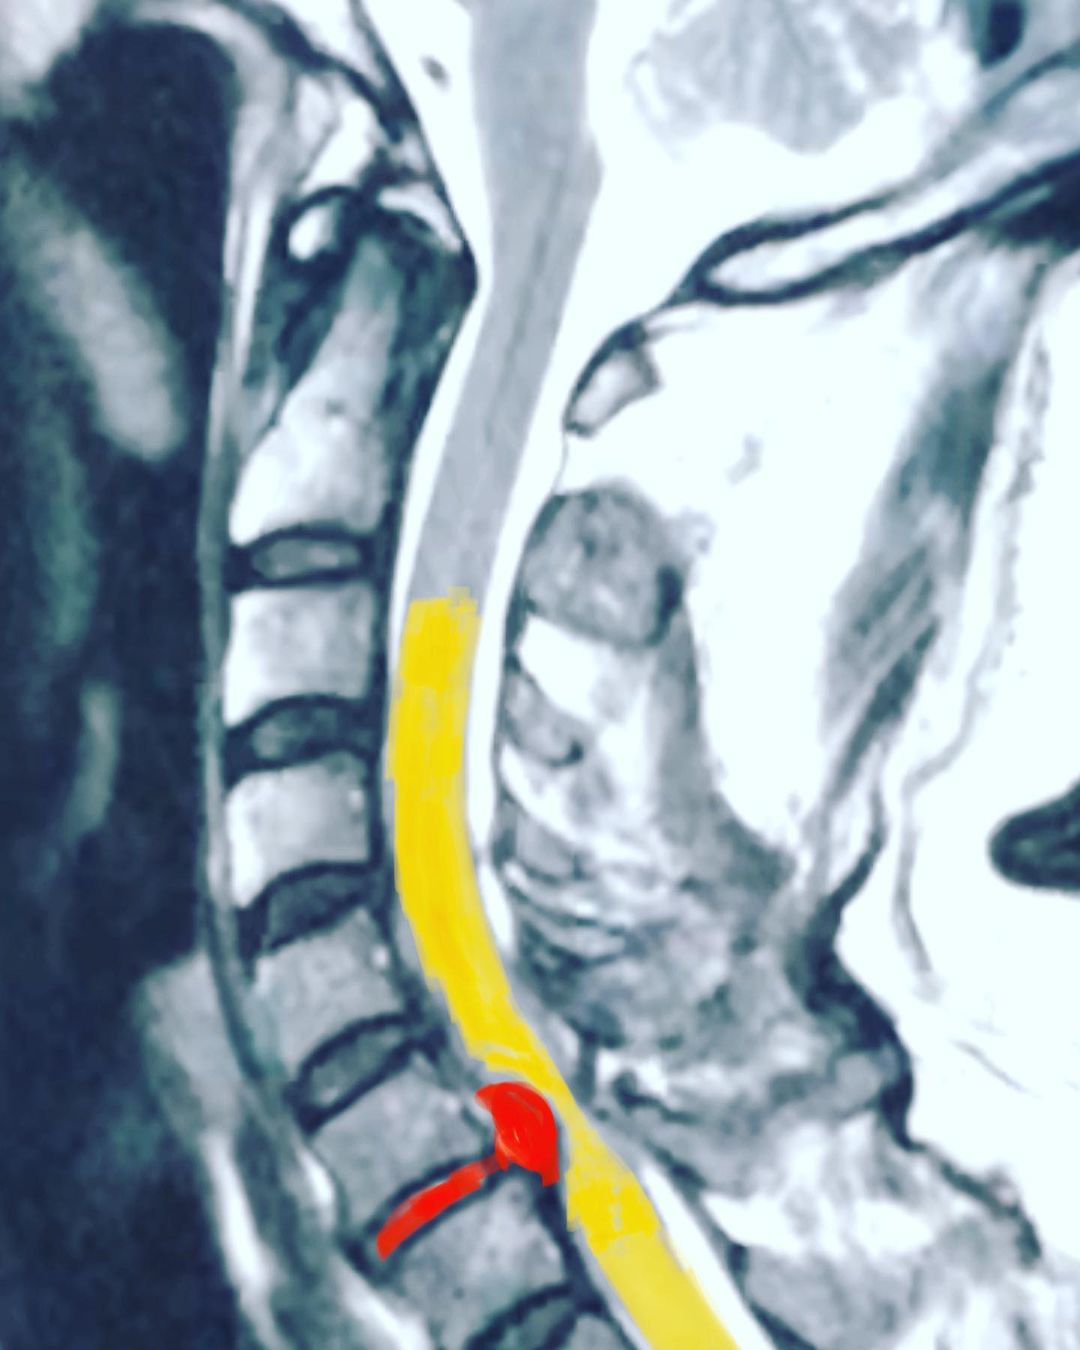

Hernia de disco

Ciática

Cirugía de la columna lumbar

Cirugía de la columna cervical